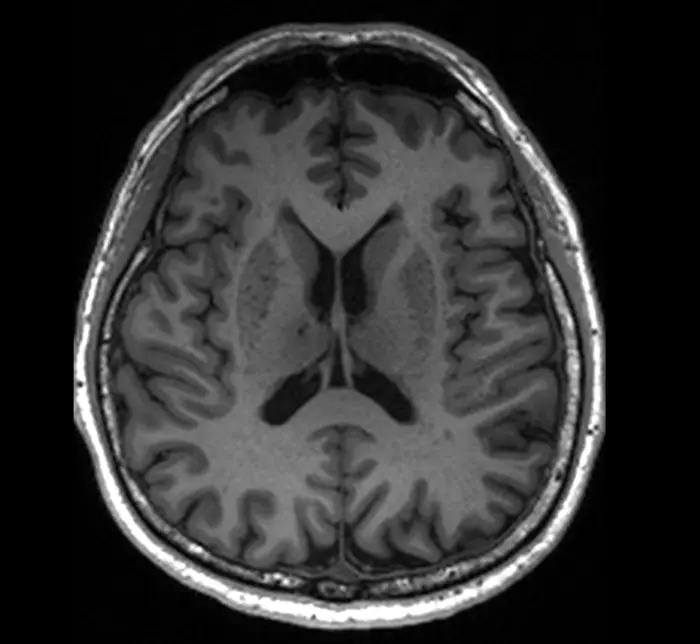

A magnetic resonance imaging image of a patient who has enlarged perivascular spaces, which are seen as dark lesions in dark grey regions around the centre of the brain.